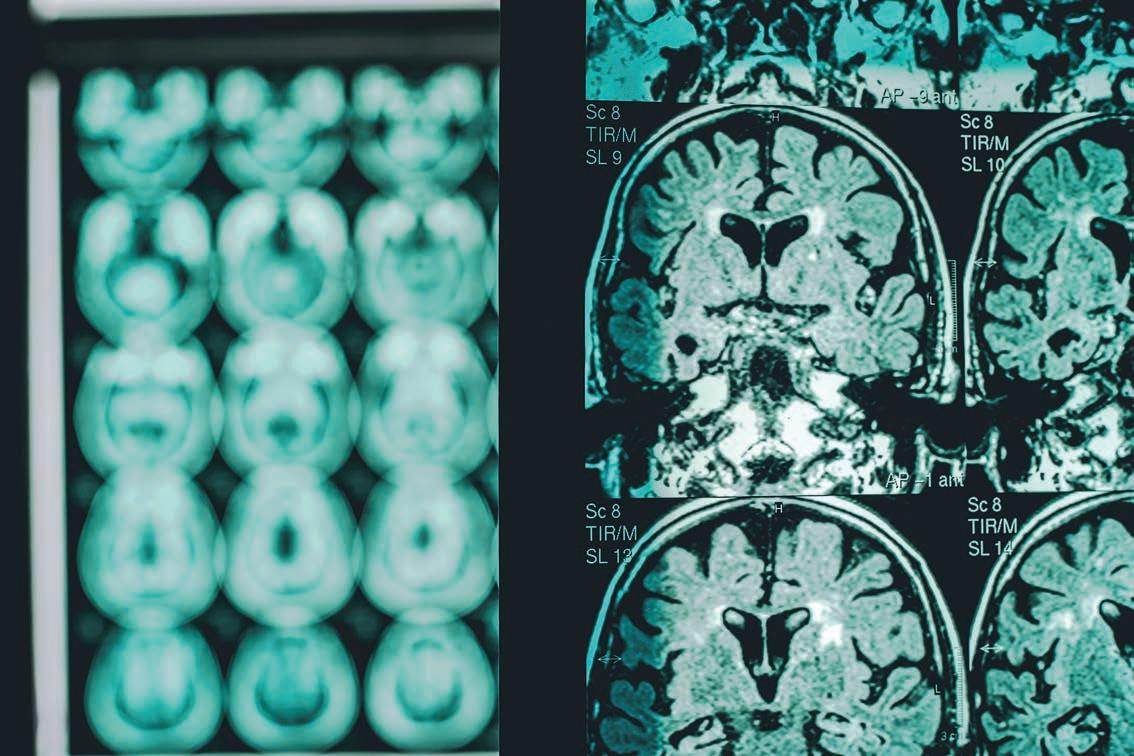

Dementia, a disease with profound effects on families, loved ones and caregivers, a ects more than 55 million people globally, including 6 million in the United States.

New research shows people can reduce their risks by making even small changes in their daily routines, for example, through exercise and eating more vegetables.

Dementia is the third-largest cause of death in the nation for people age 70 and older, and two-thirds of Americans have at least one major potential risk factor. People who smoke ve cigarettes per day have a 16% higher dementia risk than nonsmokers. People with prediabetes face a 25% increased risk, which rises to 50% with full-blown diabetes. Prolonged exposure to air pollution is also a major dementia risk factor.

Other risk factors include alcohol use, depression, high body mass index, hearing loss, hypertension, low education, physical inactivity, social isolation and

traumatic brain injury. Lock pointed out policies to reduce these risks can vary by state. For example, in Colorado, physical inactivity may not be as big of a problem

as in other states, but hearing loss is relatively high.

Lock added the goal of the research is to o er people pathways to better brain health and to give older Americans more quality time with their loved ones. e ndings were released by the new Dementia Risk Reduction Project, a collaboration between AARP, the Alzheimer’s Disease Data Initiative and the University of Washington.